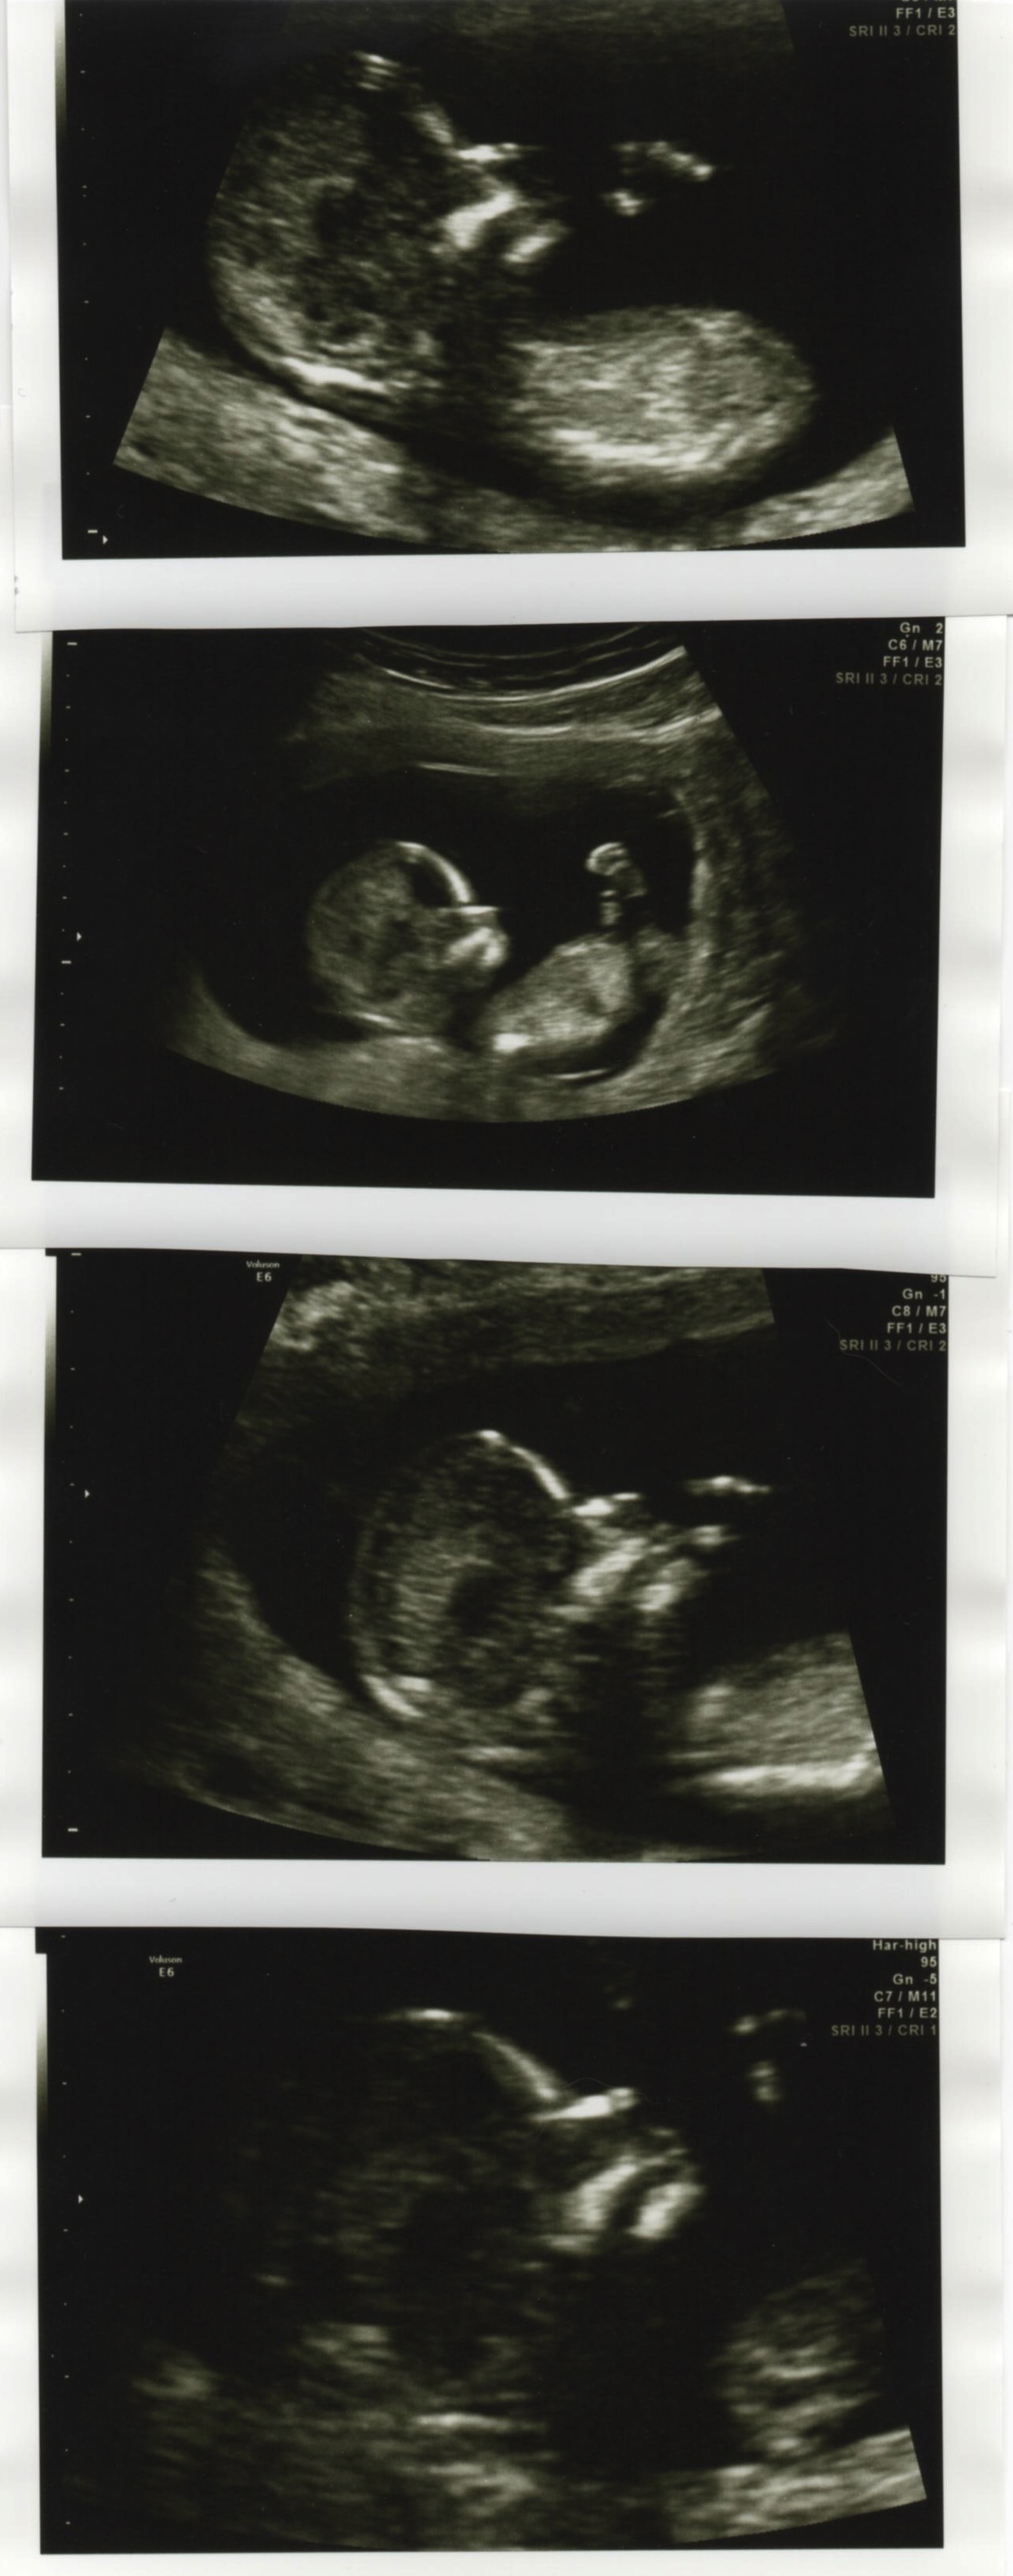

I was lucky to get a lot of sono pics from my 12 week scan. I have a thread for nub guesses and I figured I'd put one up for skull profile guesses, too.

Whaddya think, are we looking at a boy or girl? I will confirm as soon as we know! TIA!!

Attachment 14958